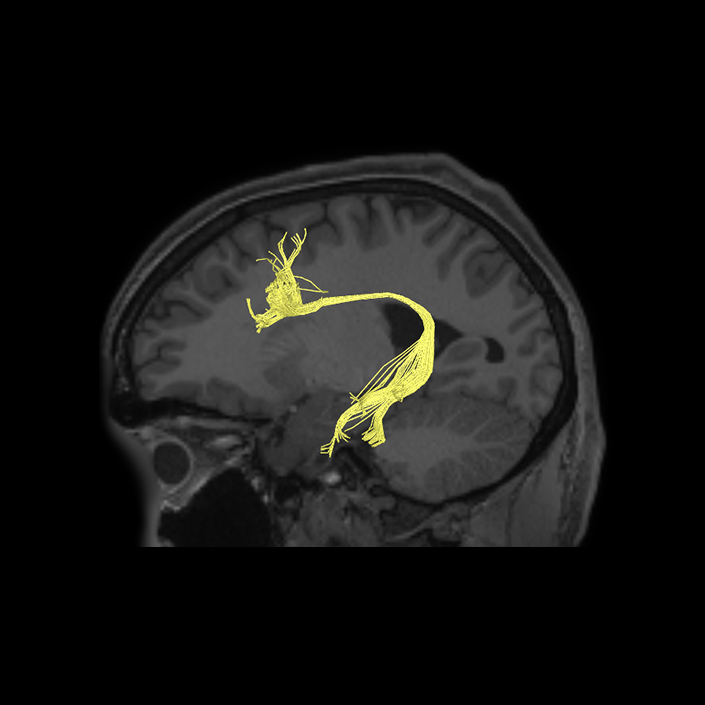

ᐅ SummaryArea SFL: part of the supplementary motor regions. Known to be hemispherically asymmetric. Specifically, the left hemisphere shows more activity when listening to stories and when a participant is matching objects based on a verbal cue. Compared to area 8BL, area SFL shows more activation when listening to a story, matching objects based on verbal cues and in social interaction settings. Compared to area s6-8, area SFL shows more activation in the left hemisphere when individuals listen to a story. In the right hemisphere, area SFL is activated insocial interaction settings and is deactivated during object feature comparison tasks. ᐅ Where is it?Area SFL (superior frontal language area) is located on the posterior medial SFG straddling over the interhemispheric cleft. ᐅ What are its borders?Area SFL borders SCEF inferiorly. Its anterior inferior neighbor is area 8BM and its anterior superior neighbor is area 8BL. Areas 6ma and s6-8 are its lateral neighbors. ᐅ What are its functional connections?Area SFL demonstrates functional connectivity to areas 8BL, 8AV, 9a, 9p, and 9m in dorsolateral frontal lobe, areas 8BM, d32, areas 44, 45, 47L, and 47s in the inferior frontal lobe, area 55b in the premotor areas, areas STSda, STSdp, STSva, STSvp, TE1a, and TGd in the temporal lobe, area PGi in the lateral parietal lobe, and areas 31pv, and 31pv in the medial parietal lobe. ᐅ What are its white matter connections?Area SFL is structurally connected to pyramidal tracts, the frontal aslant tract and contralateral hemisphere. Connections to pyramidal tracts descend through the posterior limb of the internal capsule and cerebral peduncle to the brainstem. The FAT connects SFL with the inferior frontal gyrus, terminating at parcellations 44, IFSp and MI. Contralateral connections course through the body of the corpus callosum to SCEF and 8BL. Local short association fibers connect with SCEF, 8BL, SFL and 6ma. ᐅ What is known about its function?Area SFL was subdivided from adjacent parcellations due to differences in myelin thickness and functional activity. Area SFL is known to be hemispherically asymmetric. Specifically, the left hemisphere shows more activity when listening to stories and when a participant is matching objects based on a verbal cue. Compared to area 8BL, area SFL shows more activation when listening to a story, matching objects based on verbal cues and in social interaction settings. Compared to area s6-8, area SFL shows more activation in the left hemisphere when individuals listen to a story. In the right hemisphere, area SFL is activated in social interaction settings and is deactivated during object feature comparison tasks. |

A: lateral-medial

B: anterior-posterior

C: superior-inferior

DTI image |